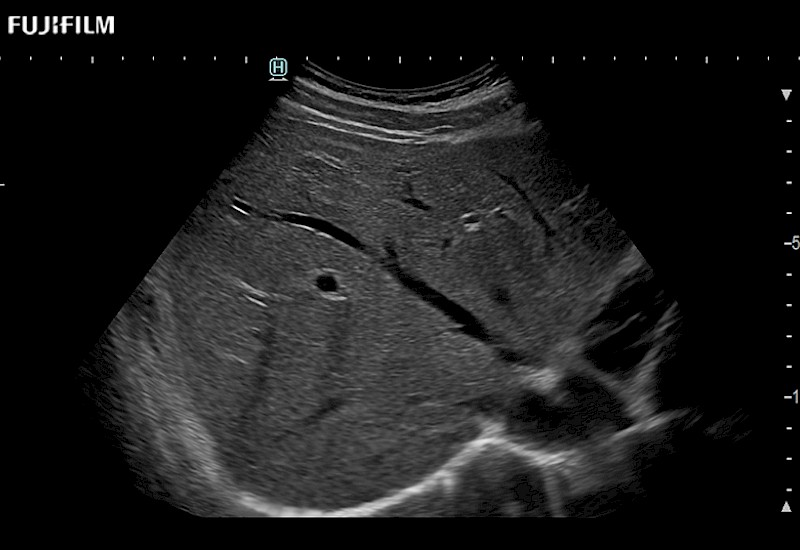

The ARIETTA 750 incorporates all of the proven technologies and functions that medical professionals have come to expect from Fujifilm Healthcare.

ARIETTA 750 is the definitive diagnostic ultrasound solution for any clinical setting - Private Office, Imaging Center, or Hospital. The ARIETTA platform provides the ultimate in clinical performance with its state-of-the-art features and large user-friendly display.

The ARIETTA 650 DI combines trusted Fujifilm Healthcare technologies and features tailored for surgical oncology.

Designed to meet the demands of surgeons, the ARIETTA 650 DI offers precise guidance. Its advanced capabilities and large, intuitive display offer accurate and efficient care in operating rooms and specialized surgical settings.